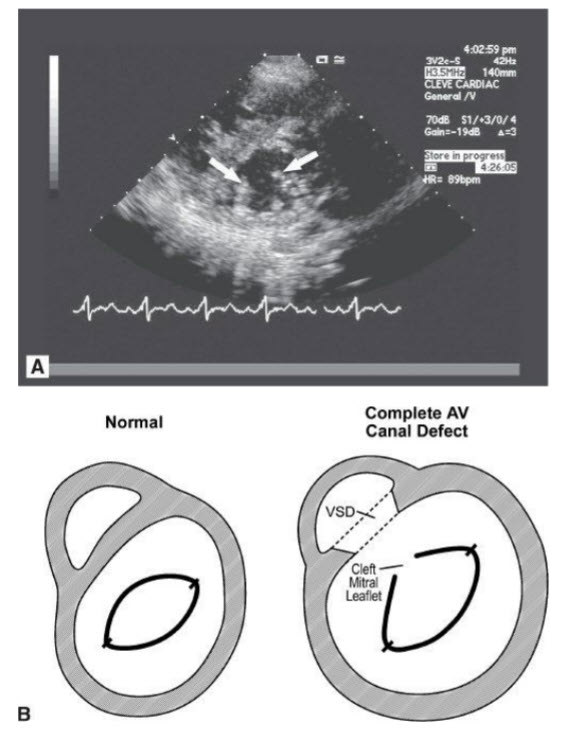

Cleft MV. The image displays an apical four-chamber view of a patient with a primum ASD. (Note Fig. B in question with color Doppler shows left-toright shunting through the ASD.) This is part of either a partial or complete AV canal defect. A complete AV canal defect includes a primum ASD, a cleft anterior mitral leaflet, and a widened anteroseptal tricuspid commissure. A partial AV canal defect is as above but without the VSD. Note that because of the long-term, significant right-to-left shunt through the ASD in this patient the right side is dilated and there is right ventricular hypertrophy from pulmonary hypertension. The short-axis view of the MV (Fig. A below) demonstrates the cleft anterior mitral leaflet, which “splits” in the center, as opposed to opening like a fish mouth as is seen with normal MVs. Figure B below is a drawing showing normal short axis of MV versus cleft MV.

A. Parasternal short-axis view of the mitral valve (TTE). B. Drawing comparing the parasternal short-axis view of a normal mitral valve to the opening of a cleft anterior mitral leaflet.